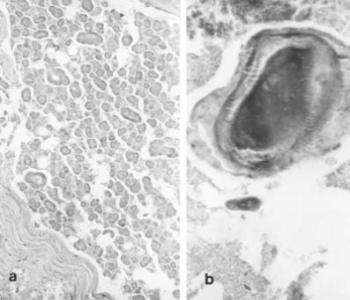

Vese- és urogenitális betegségek

Józsa László (1935) a Debreceni Orvostudományi Egyetemen végzett, majd Kecskeméten dolgozott 1968-ig. 1968–1999-ig az Országos Traumatológiai Intézet patológus főorvosa. Közben másfél évtizeden át a Tamperei Egyetem professzora. 1972-ben az Orvostudomány kandidátusa, 1980-ban akadémiai doktori minősítést szerzett. Őskórtani munkáit hosszú évtizedeken át folytatta. A millecentenáriumra megjelent könyvében a honfoglaló és Árpád-kori népesség egészségi állapotát és betegségeit foglalta össze. Sokezer csontváz és jó néhány múmia makroszkópos és szövettani-hisztokémiai vizsgálata közben a rencens patológia legmodernebb eljárásait alkalmazta. Így sikerült enzimeket, köztiállomány alkotórészeket kimutatni egyiptomi múmia bőrében, XIX. századi múmia vesegyulladásában az immunglobulin-kicsapódást. „Amikor az egyetemen, vagy munkánk közben betegségekről tanulunk, rendszerint megismerjük annak első leíróját, megtudjuk a felfedezések időpontját, ki és mikor dolgozott ki valamiféle műtéti eljárást, vizsgálómódszert. Időnként elrévedünk: vajon mit tudhattak szakmai őseink, hogyan figyelhettek fel azokra a betegségekre, elváltozásokra, amelyek az emberiség életét már a történelem ködébe vesző évezredekben is keserítették. Ezekre, és hasonló kérdéseinkre kapunk választ Józsa László egyetemi tanár könyvében, aki évtizedeken át vizsgálta a föld mélyéből napvilágra kerülő emberi maradványokat, kórboncnokként összehasonlította a napjaink emberén kialakuló elváltozásokkal. Közben szorgalmasan gyűjtötte a kérdéssel foglalkozó világirodalmi adatokat.” Dr. Cseplák György A majd kétszáz fotóval gazdagon illusztrált könyv a történelem előtti vagy a későbbi korokból származó, emberi maradványokon található kóros elváltozásokkal foglalkozik. A téma éppúgy érdekli az orvost, állatorvost, őslénykutatót, régészt, antroplógust, humánbiológust vagy a történészt, történeti demográfust, múzeológust.